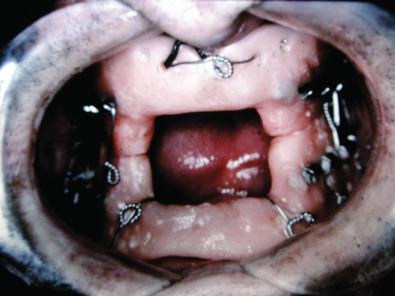

Historically, edentulous mandible fractures were treated by closed reduction. This required altering the patient’s denture and fixating the dental prostheses to the patient’s jaws and using postoperative maxillomandibular fixation (MMF). Alternatively, dental splints could be fabricated and secured to the patient and postoperative maxillomandibular fixation could be used. The dental splints could be one- or two-piece constructs. The one-piece constructed dental prosthesis is known as the Gunning splint. Treating edentulous mandible fractures with dental prostheses required additional knowledge not available to all surgeons managing facial fractures. A dental laboratory facility needed to be available in order to fabricate the acrylic prostheses after dental models had been obtained. This could be cumbersome, time-consuming and delay patient care. Additionally, the patient’s postoperative course was very difficult because of the dental appliances fixated to their jaws and the postoperative MMF. External fixators have also been used to stabilize edentulous mandible fractures as there are no teeth present. Precise anatomical reduction is often difficult with external fixators, especially in the atrophic mandible fracture with reduced bone stock. Management of edentulous mandible fractures by closed reduction techniques was difficult for the patient and had a high complication rate of nonunion ( Figs. 1.21.7–1.21.11 ).